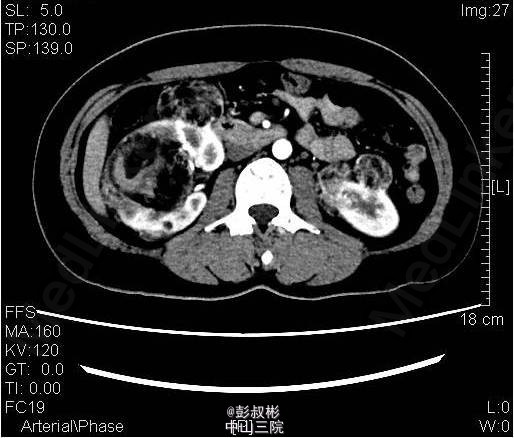

3、既往史:无特殊 4、体格检查:双肾区无红肿、隆起,左肾区叩击痛(-),右肾区叩击痛(+),左侧肋脊点、肋腰点压痛(-),右侧肋脊点、肋腰点压痛(+)。腹平软,左侧输尿管走行区压痛(-),右侧输尿管走行区压痛(-),膀胱区无膨隆,压痛阴性。 5、辅助检查:尿常规:白细胞计数27.60个/ul; 生化全套:钾3.290mmol/L;血常规:白细胞总数12.730x10E9/L,中性粒细胞绝对值9.950x10E9/L心电图、胸片正常;肿瘤抗原检查正常。ECT:右肾灌注、功能轻度降低;左肾灌注、功能基本正常。GFR:左肾为67.3ml/min,右肾为30.6ml/min。CTU:右肾体积增大,双肾可见多发大小不等结节状、团块状异常密度影,其内密度欠均匀,病灶内可见脂肪密度影,增强扫描呈不均匀强化,最大者位于右肾,约59×54mm,双肾多发错构瘤,右肾错构瘤出血。

6、入院诊断:双肾错构瘤(右肾肿物破裂出血可能) 7、处理:予心电监护、吸氧、留置尿管,引流出淡黄色尿液1600mL;急查血常规、生化未见明显异常;予抗感染、补液及营养支持治疗。拟行腹腔镜下右肾部分切除术,备右肾切除术。